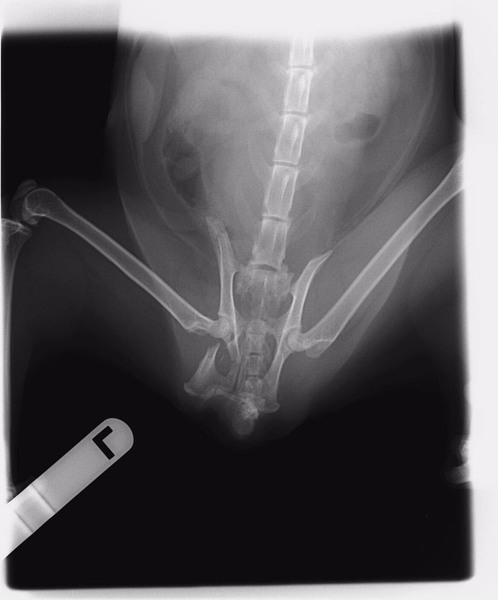

| 里親募集する理由 | 野良猫として長い間外で暮らしてきました。 運悪く事故にあい骨盤を骨折して歩けなくなっていた所をエサやりさんが発見し保護しました。 高額な医療費で手術出来ないまま放置されていたので引き取りました。 何とか寄付を集め手術も無事終わり歩けるようになりました。 |